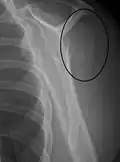

| Midshaft humerus fracture with callus formation | |

A fracture of the greater tuberosity as seen on AP X ray -

A fracture of the greater tuberosity of the humerus -

Fracture of the greater tuberosity of the humerus -